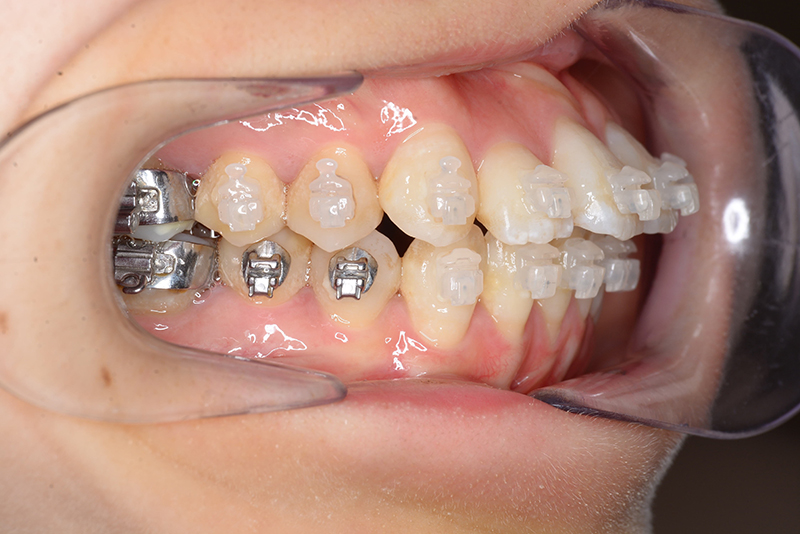

口腔内所見 over jet 4.0mm、over bite 2.0mm、臼歯関係Ⅰ級、犬歯関係Ⅱ級で上顎前歯は唇側傾斜を呈しており、上下顎前突の様相を呈していた。